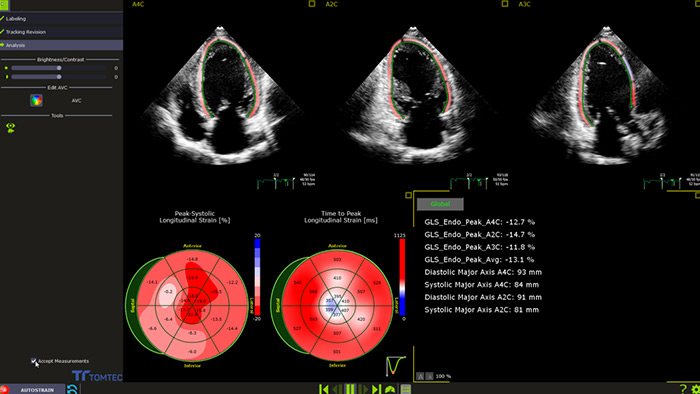

Das Management des Kardiotoxizitätsrisikos setzt eine Zusammenarbeit zwischen Kardiologen und Onkologen voraus. Im Idealfall wird mit einer kardiologischen Voruntersuchung von Patienten begonnen, denen potentiell kardiotoxische Substanzen verabreicht werden sollen.4 Bei der einfachen und überaus gängigen Beurteilung der linksventrikulären Ejektionsfraktion (LVEF) mittels 2D-Echokardiographie werden jedoch oftmals kleine Veränderungen der linksventrikulären Kontraktilität nicht erkannt. Genauere Messungen bietet die 3DEF. Beide Analysen können jedoch durch den globalen longitudinalen Strain (GLS) ergänzt werden, den am besten geeigneten Deformationsparameter, der die frühzeitige Erkennung einer subklinischen LV-Dysfunktion zulässt.4

Automatische GLS-Messung für die klinische Routine-Anwendung

Die in das Verfahren integrierte oder bei der Nachverarbeitung angewendete Funktion AutoStrain bietet eine einfache und schnelle GLS-Messung mittels Auto View Recognition und Auto Contour Placement. AutoStrain LV basiert auf einer Lernkurve von mehr als 6000 Bildern und bietet somit Zuverlässigkeit und eine reproduzierbare linksventrikuläre Strain-Messung bei der täglichen klinischen Anwendung.